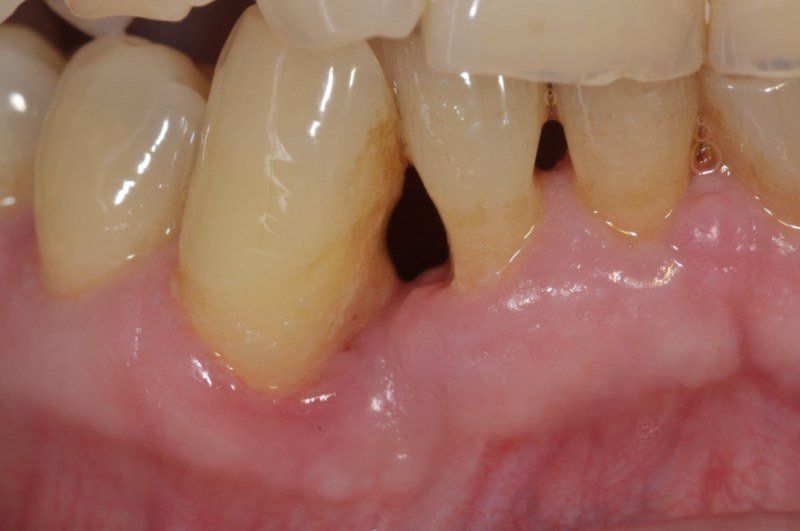

1° Caso: retrazioni gengivali